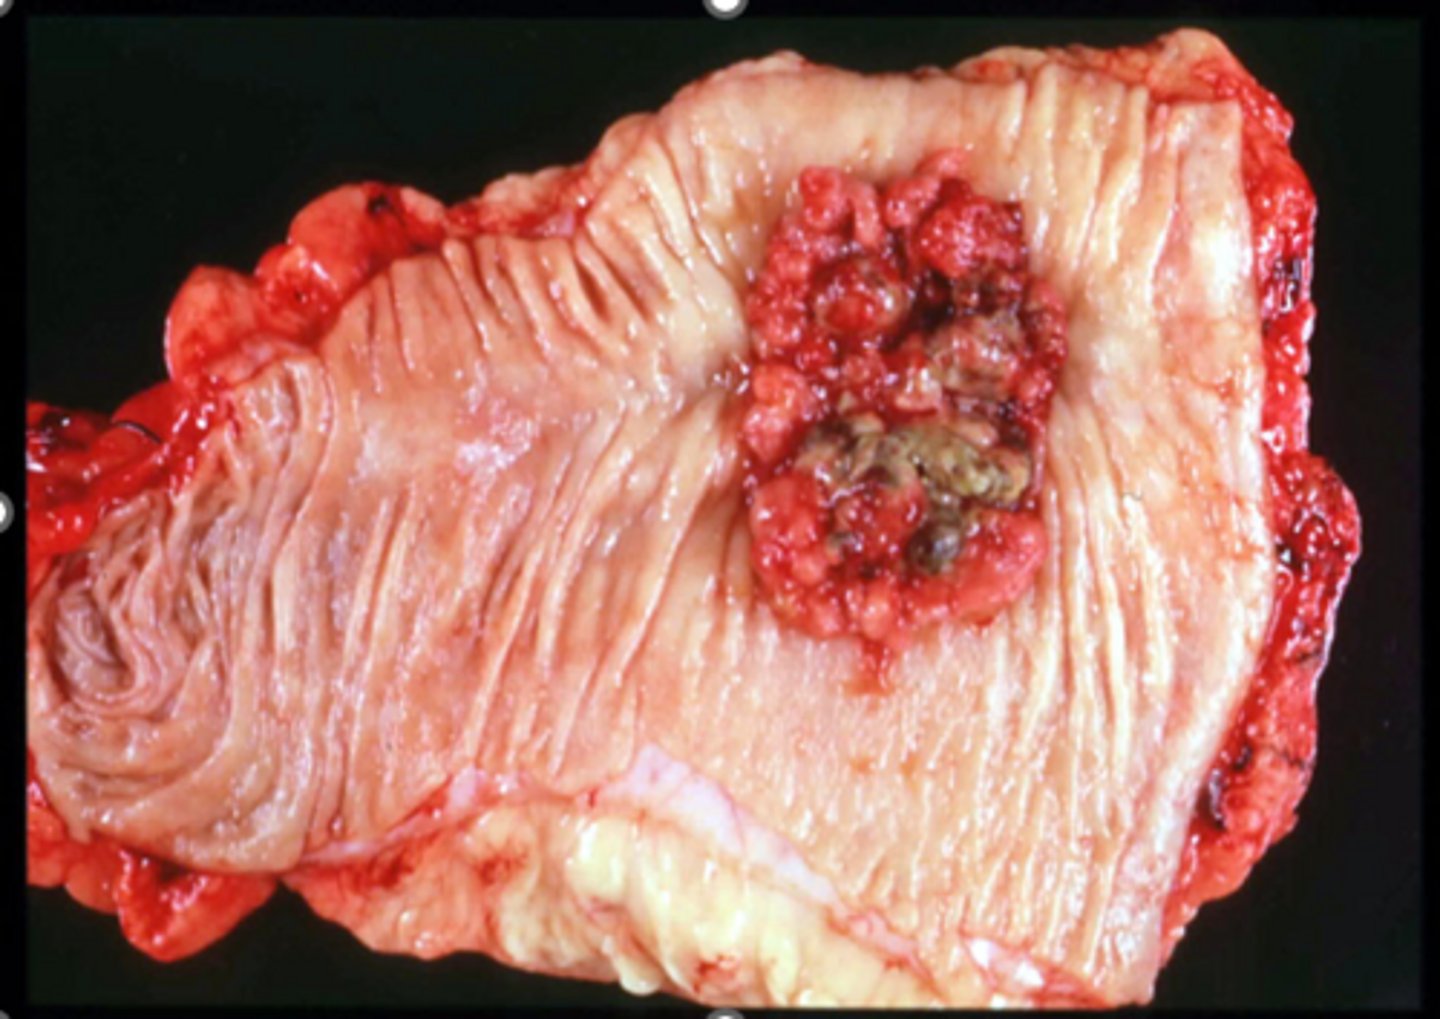

What the gross appearance of adenomcarcinoma on the right side of the colon?

a mass with blood

What is the gross appearence of adenomcarcinoma on the left side of the colon?

apple core lesion or napkin-ring appearnce casuesd by narrowing of the lumen

What are miscrospic/ histological findings of adeno carcinoma of the colon?

Well to poorly differentiated

marked desmoplasia

mucin producing

"dirty necrosis"